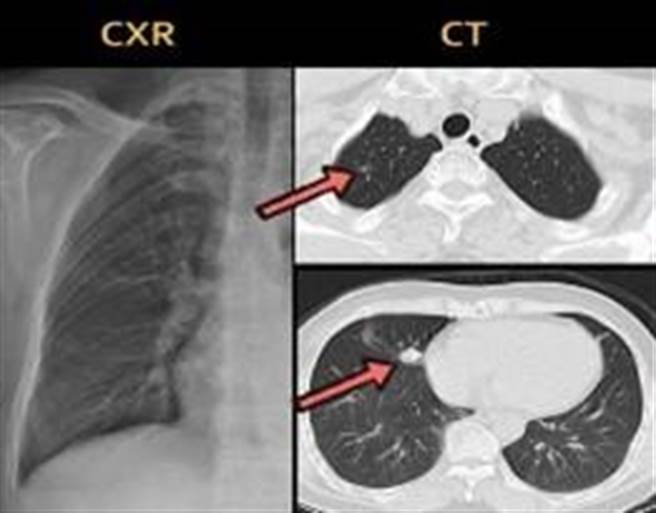

不过林妇的大肠镜检查都无异常,但血液检查的癌症指数达4.3(标准为3),医师接着安排X光及电脑断层检查,结果断层扫描发现林妇的右上肺叶有一颗0.4公分的微浸润腺癌、右中肺叶有颗1.2公分的肺腺癌;医师考虑到林妇年纪,决定以「单孔胸腔镜」微创手术切除治疗,术后血液癌症指数降为1.3,后续定期追踪。

戴硕莹表示, 我国10大死因首位为癌症,而肺癌为10大癌症死亡人数的第1名。而肺肿瘤早期症状通常不明显,往往是做其他治疗检查时意外发现的,肿瘤若大到1公分以上才会被X光侦测到,低剂量电脑断层可以侦测3至4mm大小的肺结节,侦测到的结节越小,越属于早期范围,治疗上较安全又容易根治。

反过来,X光检查侦测不到1公分以下的肿瘤,若病灶位置在不易判读的死角,会造成诊断治疗延迟,延迟3至5年后,原本1公分可能长到7公分以上,甚至是第4期肋膜转移或远端转移,晚期恶化的肿瘤,通常难以回天。